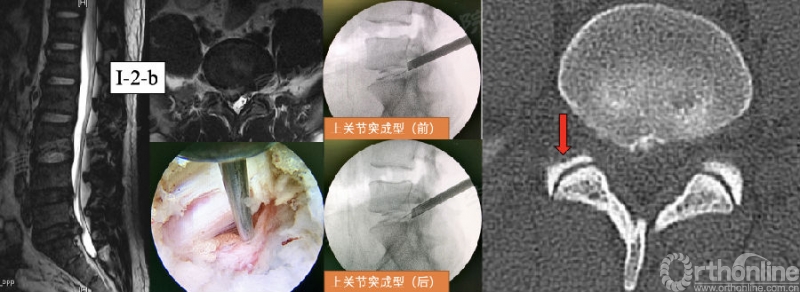

第25例:男,32岁,L5/S1 LDH(I-2-b)。

第54例:男,47岁,L5/S1 LDH(I-2-b)伴钙化。